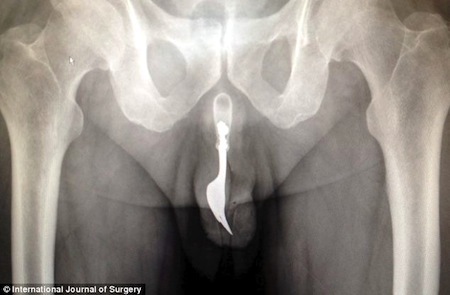

A fork in the rod [medical case report]

Some persons use a fork to eat dinner. At least one person found an alternate use for the implement:

“Urethral Foreign Body,” Krishanth Naidu, Amanda Chung, and Maurice Mulcahy, International Journal of Surgery Case Reports, 2013. The authors, at the Canberra Hospital, Canberra, Australia, report:

“Lower urinary tract foreign body insertions have a low incidence. The motives for insertion of a variety of objects are difficult to comprehend. This case warrants discussion given the great management challenge faced by the oddity and infrequency with which a fork is encountered in the penile urethra…. A 70-year-old man presents to the Emergency Department with a bleeding urethral meatus following self-insertion of a fork into the urethra to achieve sexual gratification. Multiple retrieval methods were contemplated with success achieved via forceps traction and copious lubrication…

Detail from the study:

(Thanks to investigator Sharon Trudgeon, the Canberra Times, and the Daily Mail, for bringing this to our attention.)